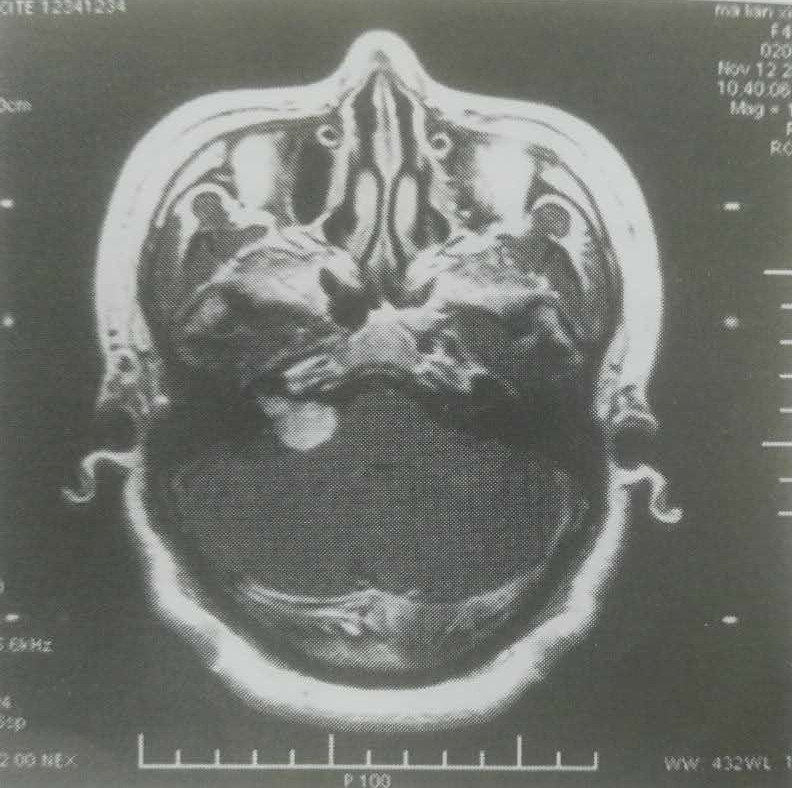

李某,女,48岁。患者10多年来无明显诱因出现右耳耳鸣,间断性出现,阵发性加重,呈轰鸣,伴听力下降,近1个月患者感四肢麻木无力,活动后加重。

MRI显示右侧桥小脑角占位性病变,诊断:右听神经瘤。2008年11月行伽马刀治疗,如下图:

50%等剂量曲线包饶病灶,边缘剂量15Gy,中心剂量30Gy。治疗后6个月复查MRI显示肿瘤中心坏死,瘤体稍增大,如下图: